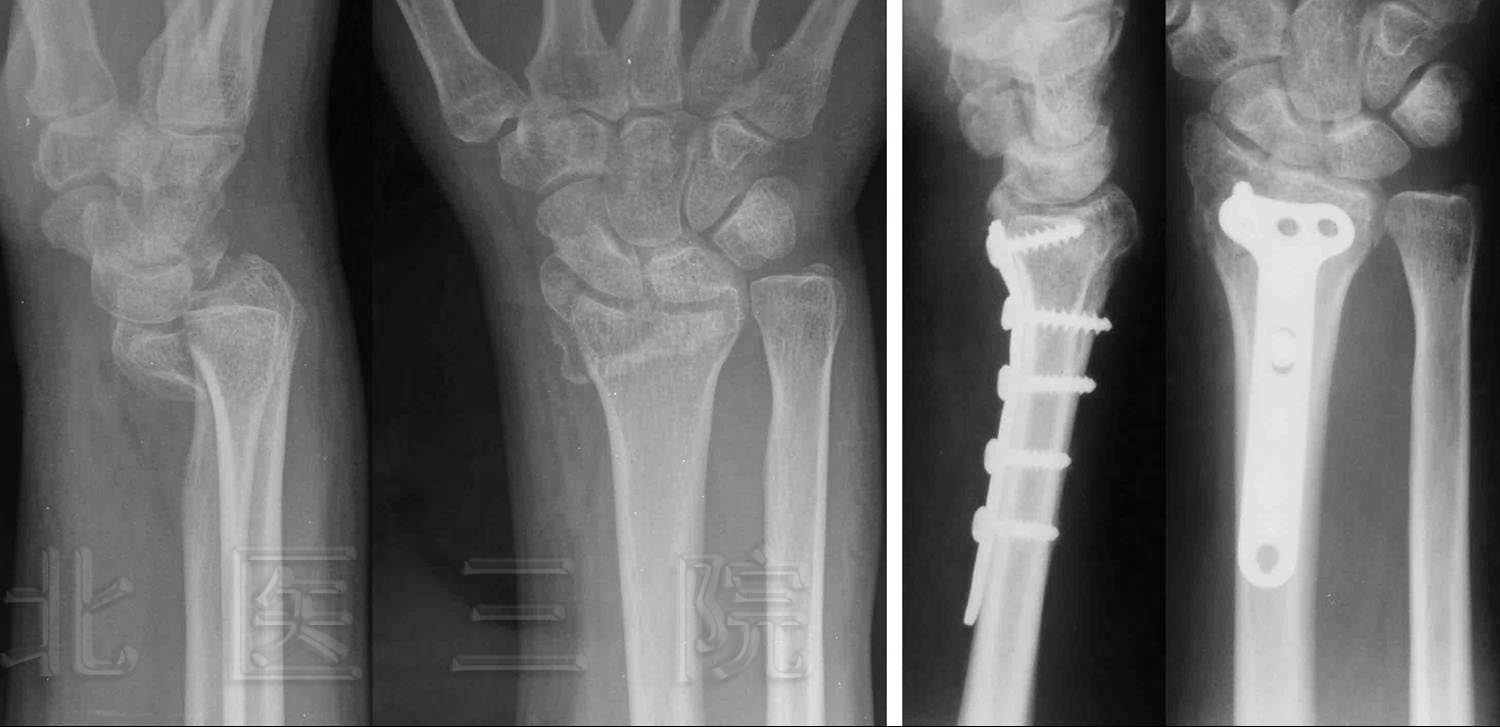

3.桡骨末端掌侧Barton骨折

图2:术后6个月,人工骨完全吸收,骨折愈合,患者左上臂活动恢复正常。

FIGURE 2: Six months later, bone union occurred and left upper arm restored to

normal movement.